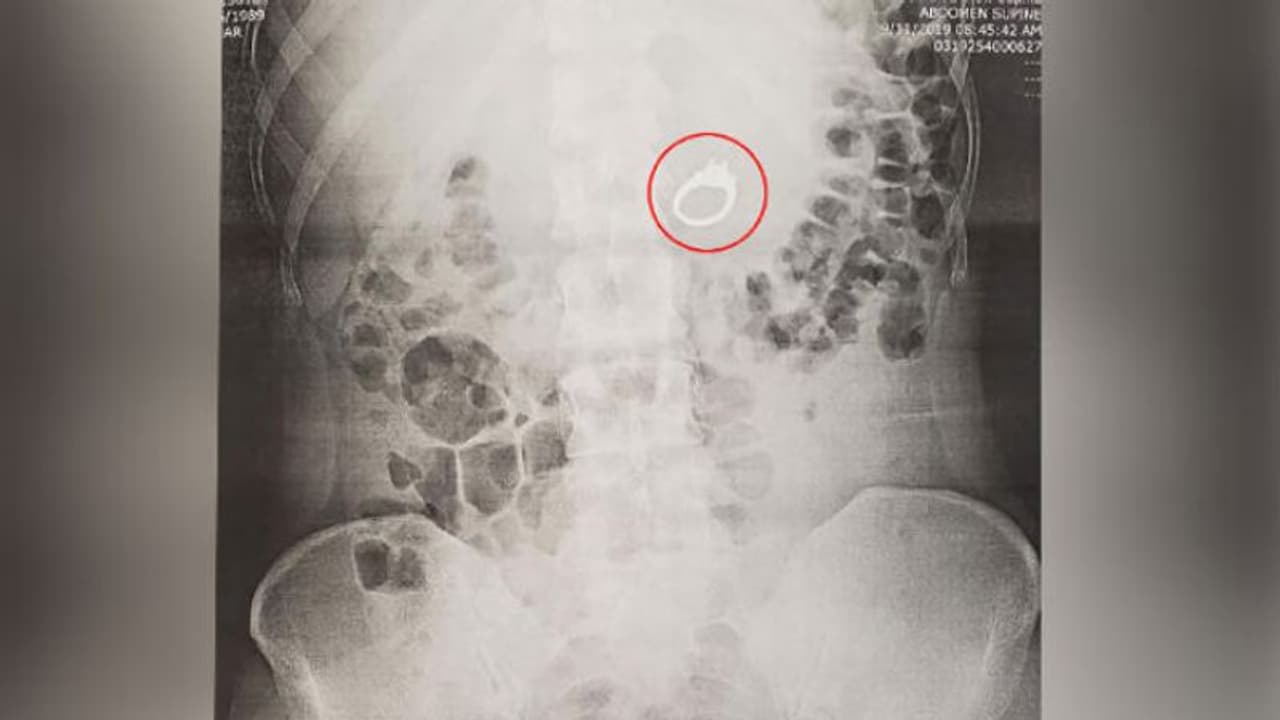

ഉറക്കത്തിനിടയില് എന്തോ സംശയം തോന്നിയെങ്കിലും അത് സ്വപ്നമല്ലേ എന്ന ആശ്വാസത്തില് ഉറക്കം തുടര്ന്നു. എന്നാല് രാവിലെ എഴുന്നേറ്റ് നോക്കിയപ്പോള് മോതിരം കാണാനില്ല. പിന്നീടാണ് സ്വപ്നത്തിന്റെ സ്വാധീനത്തില് ജെന്ന, താന് മോതിരം വിഴുങ്ങിയതായി മനസിലാക്കുന്നത്.

ഉടന് തന്നെ വിവരം ബോബിയേയും അമ്മയേയും അറിയിച്ചു. വൈകാതെ ആശുപത്രിയിലെത്തി, മോതിരം പുറത്തെടുത്തു. ഉറക്കത്തില് എഴുന്നേറ്റുനടക്കുന്ന പതിവുളളയാളായിരുന്നു ജെന്ന. ഇതിന്റെ ഭാഗമായായിരിക്കാം, സ്വപ്നത്തില് എളുപ്പം സ്വാധീനപ്പെട്ടതെന്ന് ഡോക്ടര്മാര് പറയുന്നു.